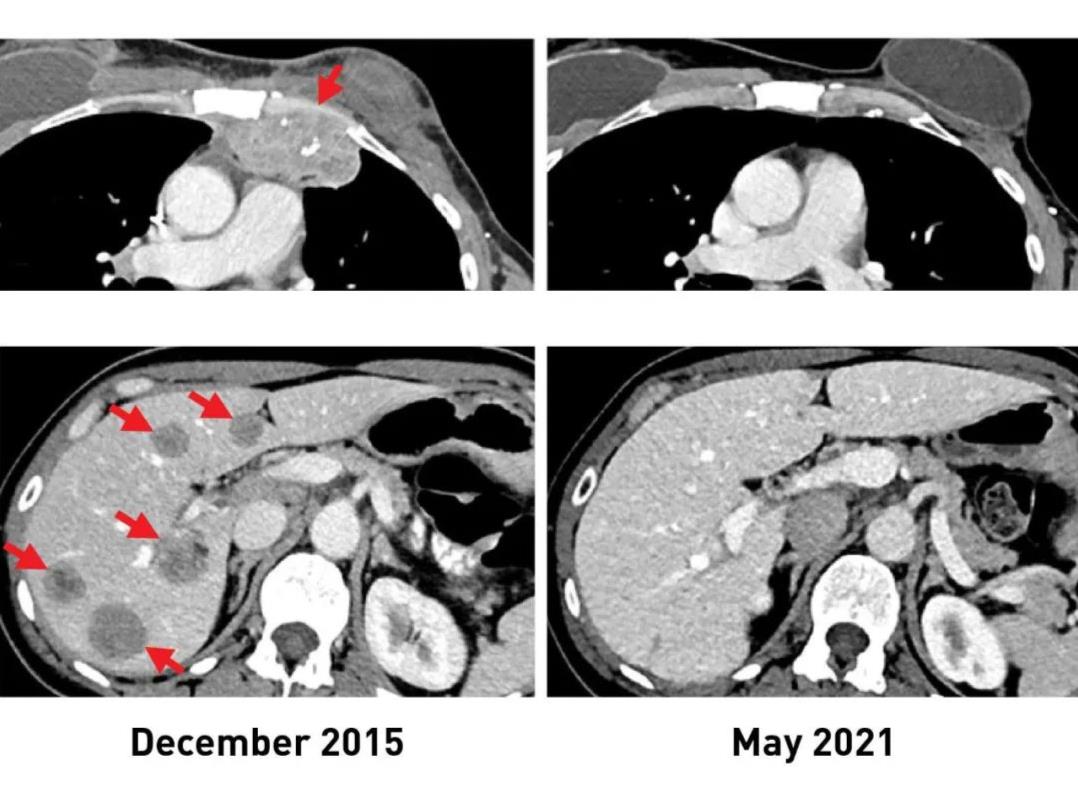

图2 一例乳腺癌患者TIL治疗前后的影像学对比

▲图源“NIH”,版权归原作者所有,如无意中侵犯了知识产权,请联系我们删除

图a:该患者治疗前(2015年12月)的影像学检查示,患者肝脏(下,左)、胸壁(上,左)处,存在转移性病变。

图b:该患者在接受免疫治疗后(2021年5月)的影像学检查示,肿瘤完全缩小,且随访5年未见新发癌症。